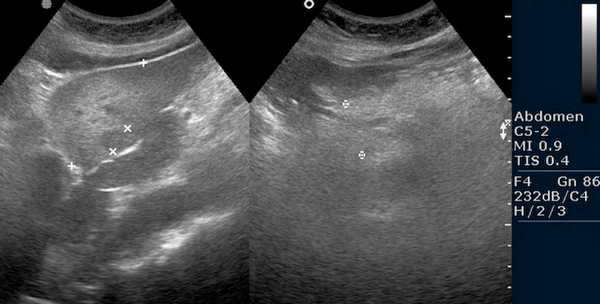

Как выглядит доля Риделя на УЗИ печени